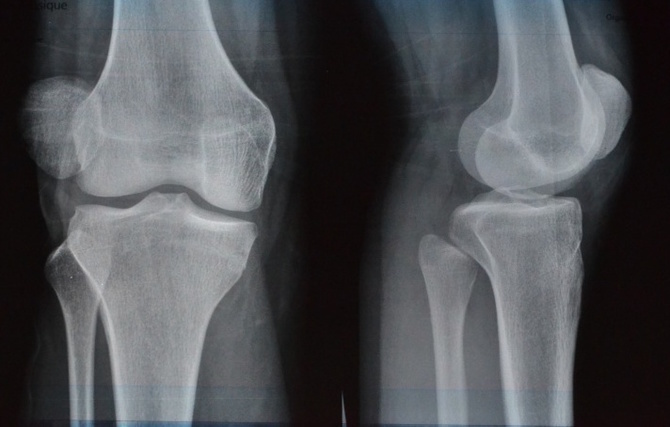

Durere de genunchi- Condromalacia rotuliana

Condromalacia rotuliana se refera la inmuierea si distrugerea cartilajului de pe partea inferioara a genunchiului sau a patelei. Este una dintre cauzele comune ale durerii genunchiului, mai ales la femei.

Condromalacia rotuliana este cauzata de o aliniere necorespunzatoare sau de pozitionarea necorespunzatoare a patelei in timp ce aceasta se deplaseaza peste femur. Cel mai frecvent simptom este o durere surda in spatele rotulei.

Si in acest caz va sfatuim sa va adresati specialistului, sa mergeti la control si sa va pregatiti de tratament.